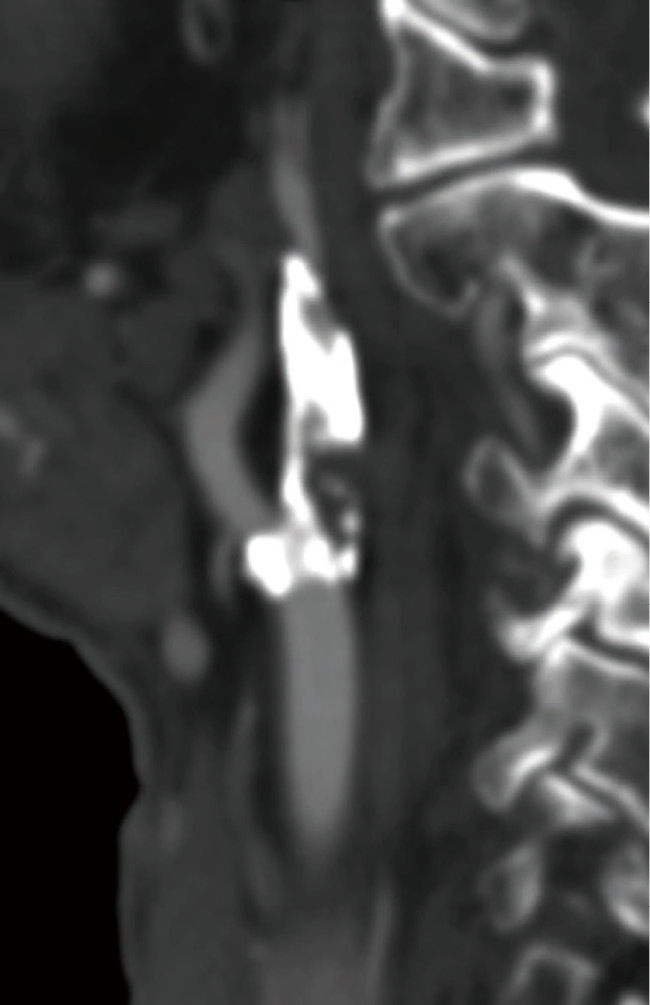

Most previous large studies of carotid artery stenting (CAS) in maintenance hemodialysis patients are old-era, do not describe the types of stents and method of protection, and their effectiveness is unknown. CAS has progressed remarkably, and tailor-made CAS is now possible in hemodialysis patients according to the lesion. We aimed to analyze the outcomes of CAS in maintenance hemodialysis patients treated in our institution.We retrospectively investigated the data of patients who underwent elective CAS in our institution between January 2012 and April 2023. Firstly, we verified the outcomes of CAS in maintenance hemodialysis patients. Secondly, the outcomes of CAS in maintenance hemodialysis patients were compared with CAS in nondialysis patients during the same period.During the study period, 212 patients with carotid stenosis underwent CAS. Among these, 18 patients undergoing maintenance hemodialysis were identified for analysis. All 18 patients underwent lesion-specific tailor-made CAS. All 18 patients were technically successfully stented with good vasodilation and improvement in stenosis. No symptomatic cerebral infarction occurred within 30 days after CAS. There was no difference between dialysis and nondialysis patients in the risk of symptomatic complications and death occurring within 30 days after surgery. There was a higher risk of hemorrhagic complications not associated with prognosis in the dialysis group (23.1% vs 1.0%, P = 0.0047). No in-stent restenosis (>50% stenosis) and ipsilateral cerebral infarction at 1 year occurred during follow-up.CAS in hemodialysis patients may be safe and effective.

以往对维持性血液透析患者进行颈动脉支架置入术(CAS)的大型研究大多年代久远,未对支架类型和保护方法进行描述,其效果也不得而知。目前,CAS 已取得显著进展,可根据病变情况为血液透析患者量身定制 CAS。我们回顾性调查了 2012 年 1 月至 2023 年 4 月期间在我院接受选择性 CAS 治疗的患者数据。首先,我们核实了维持性血液透析患者接受 CAS 治疗的结果。在研究期间,212 名颈动脉狭窄患者接受了 CAS。在研究期间,212 名颈动脉狭窄患者接受了 CAS 手术,其中 18 名接受维持性血液透析的患者被确定为分析对象。所有 18 名患者都接受了针对病变部位量身定制的 CAS。所有 18 名患者都成功地进行了技术性支架置入,血管扩张良好,狭窄情况有所改善。CAS 术后 30 天内未发生无症状脑梗塞。透析患者和非透析患者在术后30天内出现症状性并发症和死亡的风险没有差异。透析组发生与预后无关的出血性并发症的风险较高(23.1% vs 1.0%,P = 0.0047)。随访期间没有发生支架内再狭窄(狭窄程度大于50%)和同侧脑梗死。